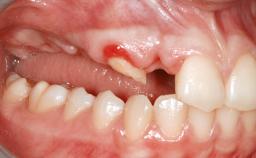

A 46-year-old woman was referred for treatment whose main complaints were mobility of her fixed partial dentures (right maxilla and left mandible) and periodontal bleeding during function. She also reported having taken systemic antibiotics to treat recurrent swelling in the area of the upper left molars. The patient had not seen a dentist for at least 2 years. She did not smoke and had no history of major systemic disease other than two minor orthopedic procedures some years back. The first-visit examination revealed poor plaque control, tooth mobility, periodontal disease, and a residual dentition widely associated with deep periodontal pockets.

Infection at Implant Site None Chronic Acute

Soft Tissue Anatomy Intact Defective

Bone Volume Horizontally and vertically sufficient Horizontally deficient Deficient vertically or deficient vertically AND horizontally